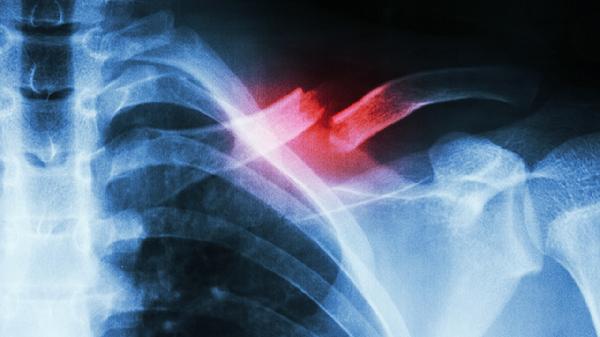

1、外伤

胸部直接撞击或挤压可能导致肋软骨损伤,引发无菌性炎症反应。患者可出现受伤部位持续性钝痛,咳嗽或深呼吸时疼痛加剧。急性期需立即冷敷并制动,疼痛明显时可遵医嘱使用布洛芬缓释胶囊、双氯芬酸钠肠溶片等非甾体抗炎药。